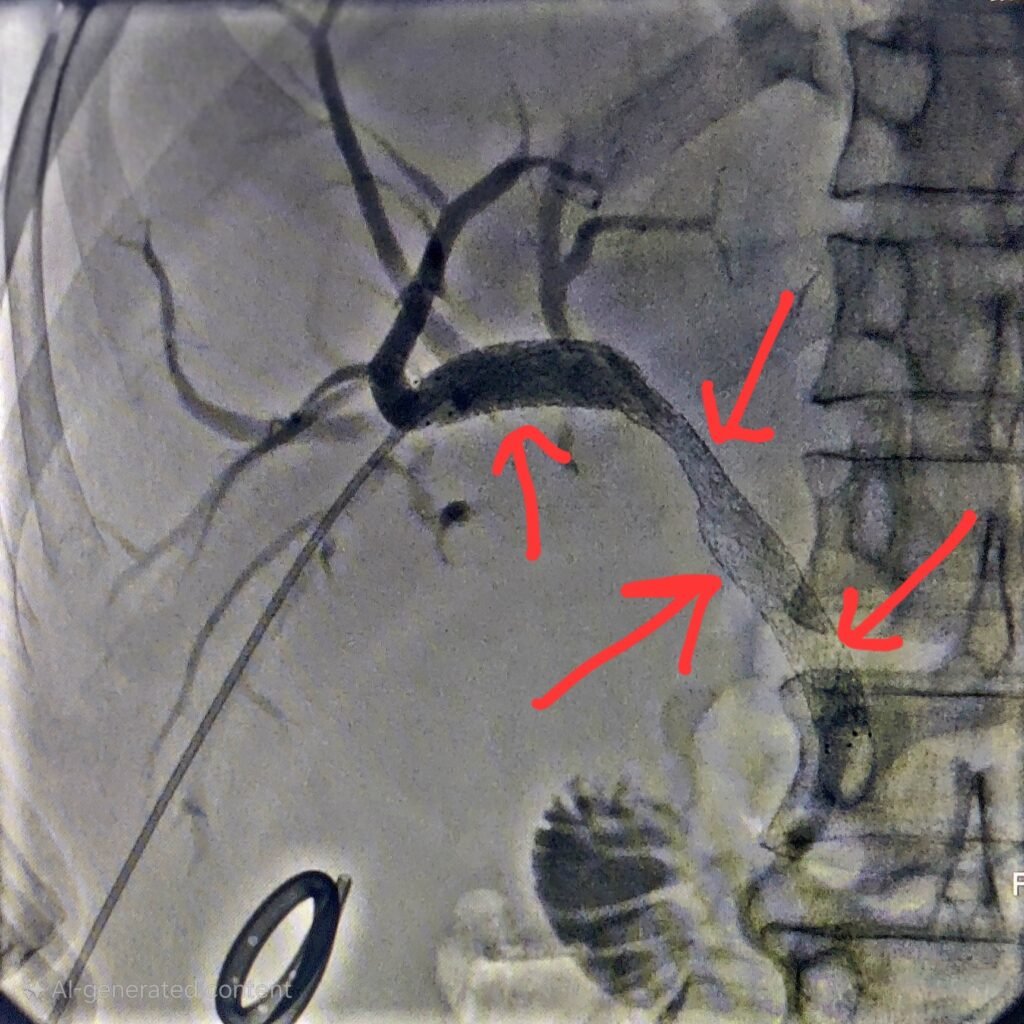

Performed under imaging guidance (Ultrasound/Fluoroscopy):

✅ Needle inserted through the skin into the bile duct

✅ Contrast dye outlines the blockage

✅ A stent is placed across the obstruction